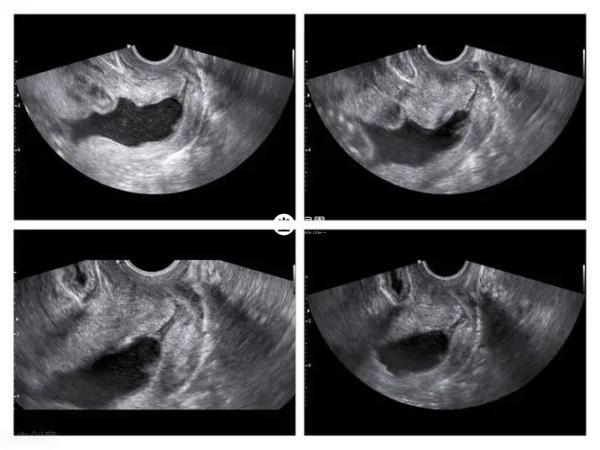

最近網傳在四維彩超檢查單子上,如果影象中出現3個亮點的話,代表可能是懷男孩,其實這樣的說法並沒有科學依據,網上流傳的那些說法也只是誤打誤撞,並不能代表這樣就可以確認是男還是女。因為可能受胎兒體位和拍攝角度以及臍帶的影響造成錯誤判斷,也有很多寶媽表示孕期通過四維數值看男女,結果出現了翻盤。女性在懷孕期間的時候需要定期去醫院進行產檢,比如b超檢查、nt檢查、四維彩超檢查等等,以此可以瞭解腹中胎兒的發育情況,不過除了關注寶寶健康,不少孕媽也想通過各種跡象來推測懷的男孩女孩,其中通過四維彩超檢查的影象可以看出男孩女孩,如果胎兒雙腿之間有三個亮點就說明是男孩,如果沒有亮點就說明是女孩。

其實彩超單上通過3個亮點看男女的方法很簡單,女性在懷孕20-24周左右,可以到醫院做四維彩超檢查,拿到檢查報告單以後,只需要看影象上胎兒雙腿之間的區域是否出現有3個亮點即可,如果有三個亮點,表示懷男孩的機率較大。